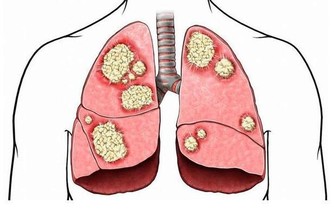

如果雙手是能一窺健康的門戶,那位於手足之端、也就是經脈終始點的井穴,就是身體與外界溝通的窗口。《黃帝內經。靈樞》將井穴喻為水之源頭,是精氣所出的部位,對於調節臟腑、氣血、經脈之氣有相當重要的作用。裡頭也提到,「病在臟者取之井」。顯見,透過井穴,可以治療相應臟腑的疾病。

井穴有清熱、醒腦、安神的作用,平時醫師會藉由放血、針灸達到治療效果,中醫則建議,一般民眾平時可以透過井穴按摩來保養身體,精神不濟時,開過十指井穴也能活絡臟腑、重拾元氣。